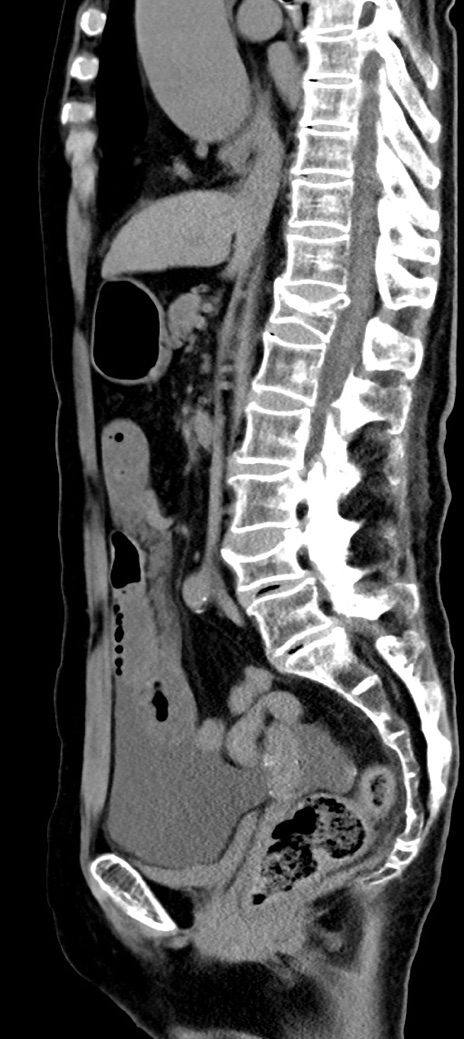

冠状断像

【症例】90歳代女性

【主訴】腹痛・嘔吐

【現病歴】 食欲低下、嘔吐があり昨日他院受診。肺炎と診断され入院となる。入院後より腹部全体に圧痛あり。胃管留置され経過みていたが、症状持続するため、

当院転院となる。

【既往歴】胸椎圧迫骨折、胆石症

【身体所見】腹部:中央に激痛あり、圧痛あり、反跳痛不明

【データ】WBC 17100、CRP 18.82